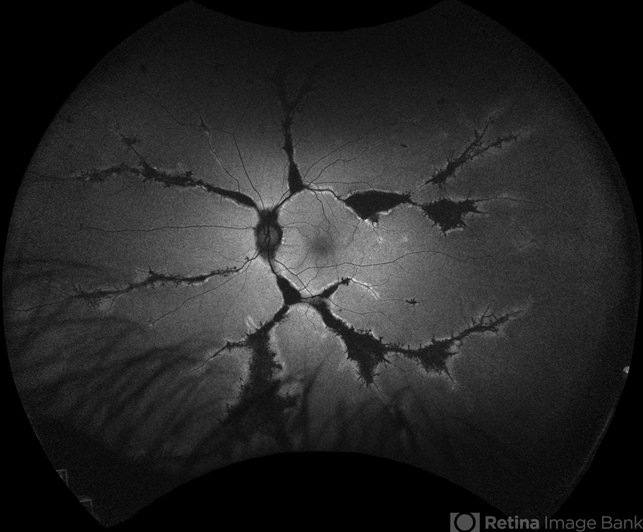

- Fundoscopy of a 42-year-old asymptomatic man with pigmented paravenous chorioretinal atrophy. Pigmented paravenous retinochoroidal atrophy (PPRCA) is a rare disorder of unknown etiology. The disease is characterized by pigment accumulation along the distribution of retinal veins. The findings are usually incidental with minimal effect on vision.